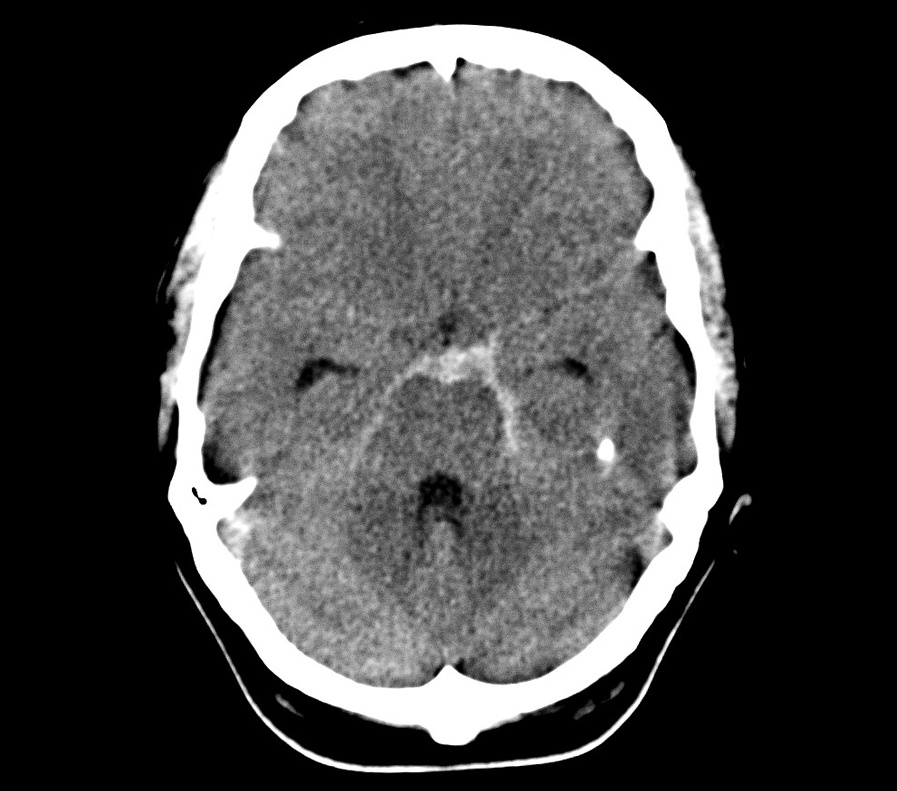

В широком смысле инсульт — это повреждение тканей мозга в результате нарушения кровообращения. По механизму воздействия его принято делить на два типа: ишемический, при котором клетки мозга недополучают крови и отмирают, и геморрагический, когда крови, наоборот, слишком много, она выходит из кровеносных сосудов и заливает часть мозга. В зависимости от места кровоизлияния геморрагический инсульт делят на внутримозговой и субарахноидальный; при последнем кровь попадает в пространство между оболочками мозга, в норме заполненное спинномозговой жидкостью.

Если инсульт уже происходит, задача врачей — восстановить кровоснабжение мозга при ишемическом сценарии или прекратить кровотечение и избавиться от его последствий при геморрагическом инсульте. При ишемии главное — избавиться от тромбов с помощью препаратов. Чем быстрее это будет сделано, тем меньше клеток мозга пострадает от недостатка кислорода и тем ниже риск серьезных осложнений и лучше прогноз. При геморрагическом инсульте медикаментозно снижают давление, чтобы минимизировать количество крови, которое попадет в мозг, а в тяжелых случаях удаляют кровь и останавливают кровотечение хирургическим путем.